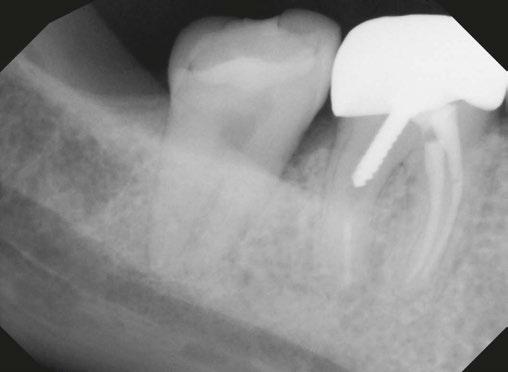

Case 1: Pre-op and diagnosis: A 68-year-old female presented with localized vestibular swelling buccal to tooth No. 30. No. 30 had been symptomatic for a few days, but the swelling started to alarm the patient and caused her to seek treatment. Upon evaluation, No. 30 was diagnosed as necrotic pulp with acute apical abscess. Two treatment options were discussed with the patient: 1) Tooth No. 30 non-surgical root canal therapy or 2) Tooth No. 30 extraction. The patient elected tooth No. 30 non-surgical root canal therapy (NSRCT). A pre-op Small FOV CBCT revealed a heavily calcified pulp chamber and calcified canals and a radix entomolaris. The CBCT revealed PARL’s at the apex of the mesial, distal, and radix entomolaris roots with the lesion extending coronally into the furcation. The patient was advised before treatment that this would be a very challenging case, and No. 30 NSRCT would be given a guarded prognosis, but she chose to proceed with No. 30 NSRCT. Treatment: No. 30 NSRCT, the patient was anesthetized with 68 mg Lidocaine with 0.034 mg EPI via IAN and 68 mg Septocaine with 0.017 mg EPI via buccal infiltration. Rubber dam isolation was utilized, and access was prepared through the PFM crown. 4 canals were located and then immediately after identification of the canal orifices, a platform was created with Soundseal, and the GentleWave Cleanflow handpiece was utilized to help break up the calcified tissue and negotiate each canal, alternating between a pathfile to slowly negotiate the coronal half of the canals and then running the GentleWave CleanFlow Procedure Instrument for 30-40 seconds to remove the accumulated debris. By alternating between files and the CleanFlow with GentleWave, all 4 canals were negotiated to length, and patency was achieved. The final working lengths were between 23 mm-24.5 mm for all 4 canals. All canals were instrumented to a Master Apical File of 20/.04 and obturated with high-flow BC Sealer. By utilizing the GentleWave and High-Flow BC Sealer, the apical delta of the distal root was cleaned, disinfected, and obturated in ways that would not have been possible with traditional endodontic therapy. Post-op: The patient was called 24 hours after treatment and reported she was pain-free, the swelling had reduced, and she was doing well.

9 endopracticeus.com Volume 17 Number 1 COVER STORY